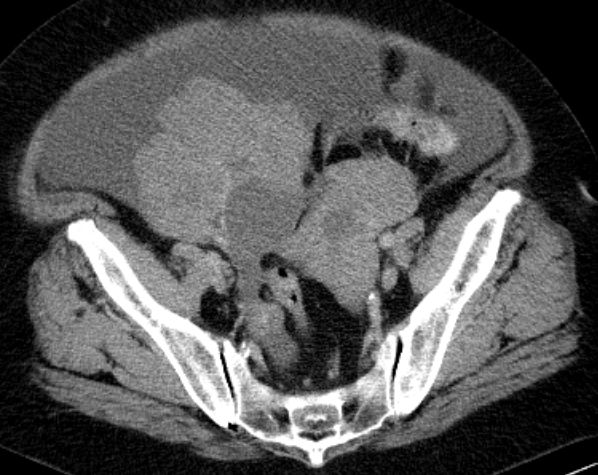

73-jährige Frau mit Ascites, Pleuraerguss links und Unterbauchtumor.  Das Netz ist komplett in einen Omental-Cake umgewandelt. An der Zwerchfellkuppe miliare Tumoraussaat.

Beide Adnexe in knapp kindskopfgroße blumenkohlartige Tumoren umgewandelt.

Im Douglas finden sich pararektal mehrere bis zu pflaumengroße Tumorknoten.